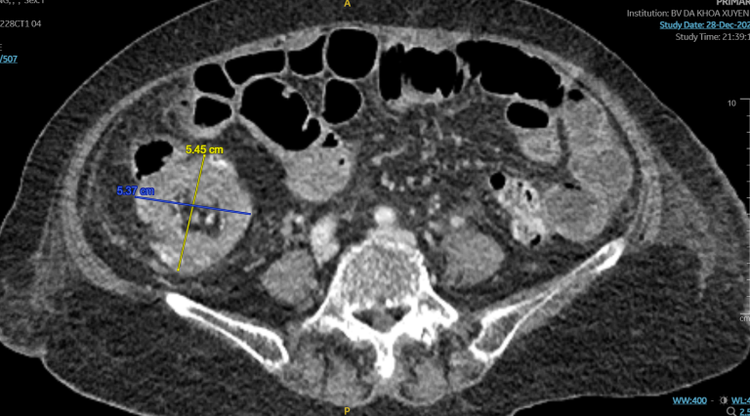

| Hình ảnh khối u trên CT - Ảnh BVCC |

Dựa trên triệu chứng bệnh, các bác sĩ nhận định đây là bệnh cảnh tắc ruột điển hình ở bệnh nhân lớn tuổi do khối u ống tiêu hóa. Người bệnh được chỉ định chụp CT-Scanner bụng chậu phát hiện một khối lồng ruột non vào đại tràng tại góc hồi – manh tràng, khối lồng hồi manh tràng do u có kích thước 5,45×5,37cm.